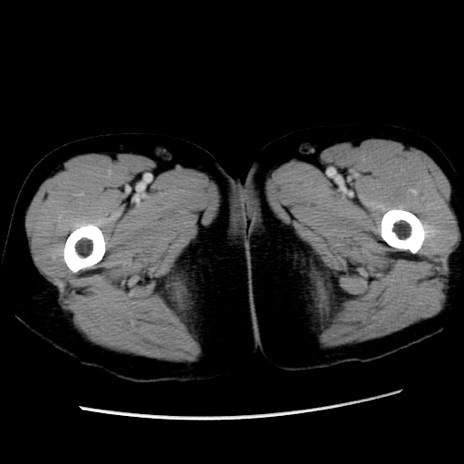

症例10(横断像)

【症例】 50歳代女性

【主訴】 腹痛

【現病歴】前日生レバーを食べた。今朝に排便あり。 昼前に突然発症の腹痛を生じ、当院救急外来を受診した。

【既往歴】 子宮筋腫にてで子宮全摘後

【身体所見】 意識清明、腹部:平坦、軟、下腹部やや左を中心に圧痛・反跳痛あり、筋性防御あり

【データ】WBC 7800、CRP 0.07